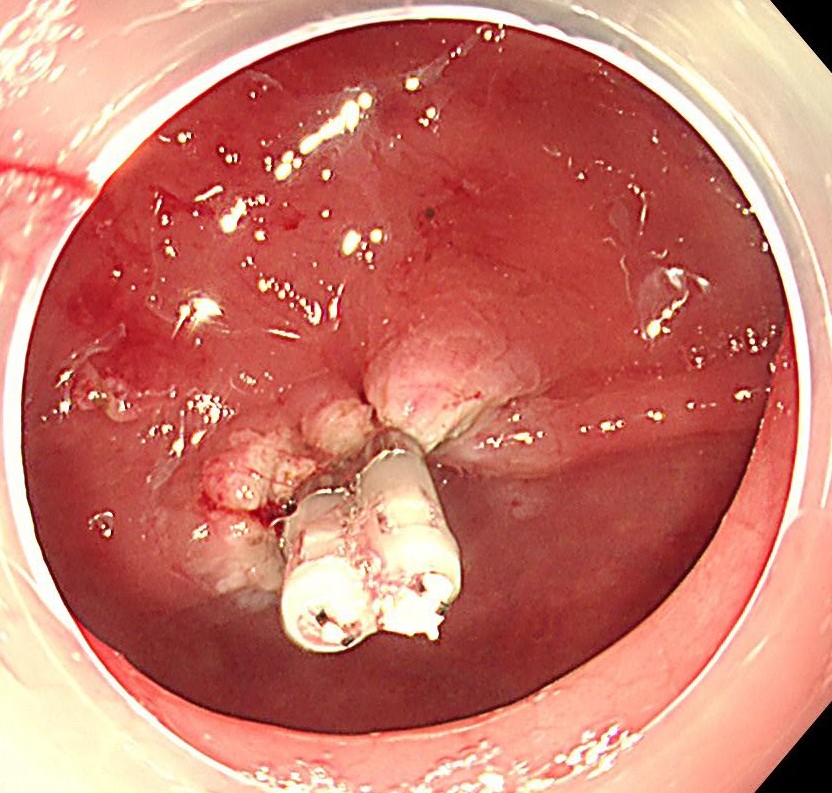

止血確認後、クリップで血管縫縮し、完全止血します。